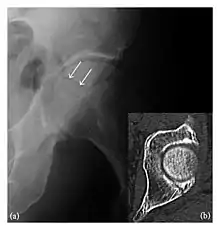

Occult osseous injuries may result from a direct blow to the bone by compressive forces of adjacent bones against one another or by traction forces during an avulsion injury. Lesions in the tibial plateau, hip, ankle, and wrist are often missed. In a tibial plateau fracture, any disruption of the posterior and anterior cortical rims of the plateau should be sought. Impaction of subchondral bone will appear as an increased sclerosis of the subchondral bone (Figure 1). In the hip, posterior acetabular fractures also present subtle radiographic findings. The acetabular lines should then be carefully examined keeping in mind that the posterior rim, which is harder to see on X-rays, is more frequently fractured than the anterior rim (Figure 2). In the wrist, detection of carpal bone fractures is often challenging, with up to 18% of scaphoid fractures radiographically occult. Carpal fractures, especially the scaphoid, are associated with the risk of avascular necrosis. In apparently normal wrist radiographs from symptomatic patients, if there is history of a fall on an outstretched hand with pain in the anatomic snuffbox, suggesting scaphoid injury, the initial examination with posteroanterior, lateral, and pronation oblique views must be complemented by other specific views such as supination oblique and the "scaphoid" view A careful examination of cortices for evidence of discontinuity or offset and cancellous bone for lucency is necessary (Figure 3).[1]

a

b

c

Figure 3: A 26-year-old man presenting with wrist pain after being assaulted. (a) Initial anteroposterior radiograph shows a subtle linear lucency within the scaphoid extending to the scaphocapitate articular surface that was overlooked (arrow). (b) Initial "scaphoid" view was negative. (c) Followup anteroposterior radiographs, 12 days later, shows obvious scaphoid fracture (arrows).[1]